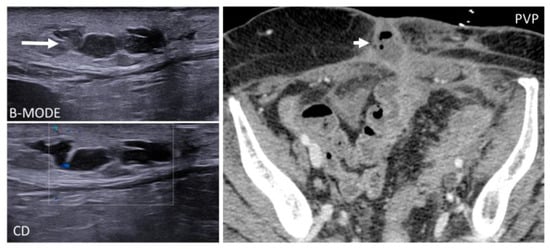

Abdominal wall abscesses present on US as superficial fluid-filled complex lesions, with ill-defined margins, predominantly hypoechoic to surrounding muscles [7,8]. Peripheral hyperemia can be seen on Color Doppler US (CDUS) [3] (Figure 1). To define the extent of the abscess, contrast-enhanced CT and MR could be used in severe cases.

Pseudoaneurysms, or false aneurysms, originate from the disruption of intimal and medial layers of an arterial vessel, after traumas, infections, or iatrogenic procedures [30,31,32]. On US, pseudoaneurysms are anechoic tubular structures, with thin walls [30,31] and turbulent Doppler flow (“yin–yang” appearance).

CT angiography is the gold standard for the diagnosis, as it precisely depicts the vascular structures involved [31] and demonstrates the integrity of the pseudoaneurysm sac (Figure 9), which should be smooth unless an infection superimposes.